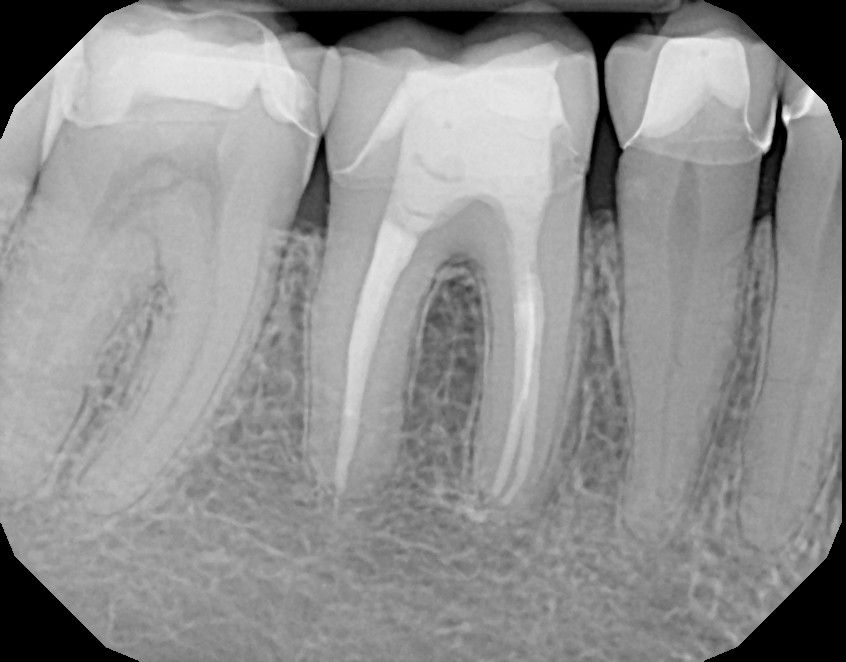

Der betroffene Zahn wird betäubt und mithilfe von Kofferdamm, einem elastischen Spanngummituch, von der Mundhöhle abgeschirmt. So ist eine schmerzfreie Behandlung möglich, bei der Ihnen keine Desinfektionslösungen in den Mund laufen und gleichzeitig auch keine Bakterien aus dem Speichel in den offenen Zahn eindringen. Falls erforderlich, wird Karies entfernt und der Zahn mit einem vorbereitenden Aufbau abgedichtet. Danach wird die Nervhöhle eröffnet, und die Eingänge in die Wurzelkanäle werden dargestellt. Nun werden alle Kanäle mithilfe der Elektrometrie ausgemessen, damit alle folgenden Maßnahmen in der richtigen Länge bis zur Wurzelspitze durchgeführt werden können. Dann werden die Wurzelkanäle mit hochelastischen Feilen aufbereitet, damit alles infizierte Gewebe und die Bakterien entfernt werden. Desinfizierende Spülungen helfen dabei. Abschließend wird das Kanalsystem mit allen seinen Abzweigungen und Einziehungen mit Laserlicht desinfiziert. Damit ist die Aufbereitung abgeschlossen. Jetzt werden die Wurzelkanäle mit einer Kombination aus einem biokeramischen Versiegeler und Füllspitzen aus Guttapercha gefüllt. Die Guttapercha wird dann durch Erwärmen im Kanal erweicht und kann an die Kanalwände angedrückt werden. So erreichen wir einen dauerhaft Bakteriendichten Verschluss. Zum Abschluss wird der Zahn mit einer fest verklebten Füllung versorgt.

Die Erfolgsaussichten für eine mit höchster Präzision durchgeführte Wurzelkanalbehandlung liegen bei bis zu 96 %. Ob ein Zahn durch eine Wurzelkanalbehandlung gerettet werden kann, ist einerseits davon abhängig, wie stark der Zahn bereits geschädigt ist und wie komplex der Verlauf der Wurzelkanäle ist, und andererseits, wie qualifiziert, erfahren und modern ausgestattet der oder die Behandler/in ist. Der Einsatz des OP-Mikroskops mit einer bis zu 24-fachen Vergrößerung ermöglicht es uns, auch feinste Strukturen im Zahn zu erkennen und zu behandeln, z. B. kleine zusätzliche Kanälchen. Modernste Techniken bei der Vermessung, der Aufbereitung, der Desinfektion und der Füllung der Wurzelkanäle sichern die Qualität unserer Wurzelkanalbehandlungen. Dr. Karin Benz hat sich durch zahlreiche Fortbildungen und langjährige Erfahrung auf dem Gebiet der Endodontie spezialisiert und führt die Behandlungen mit großer Empathie und höchster Sorgfalt aus.

Den dauerhaften Erfolg der Wurzelkanalbehandlung sichern wir mit regelmäßigen Röntgenkontrollen ab.

Ziel der Wurzelkanalbehandlung ist es, das Wurzelkanalsystem so zu reinigen und zu desinfizieren, dass das infizierte Gewebe restlos entfernt wird. Anschließend werden alle Hohlräume mit einer kompakten Wurzelfüllung versiegelt, damit kein Raum für erneute Entzündungsprozesse bleibt. Der Zahn wird dann bakteriendicht verschlossen und später meistens mit einer Krone oder Teilkrone aus Keramik stabilisiert, damit er nicht auseinanderbrechen kann.

• Verwendung modernster Versiegelungssystem: Das Wurzelkanalsystem wird verschlossen, indem ein spezielles Versiegelungsmaterial (Sealer) an die Kanalwände aufgetragen wird. Das muss bioverträglich und schrumpfungsstabil sein. Zusätzlich werden exakt angepasst Füllstifte aus Gutta percha eingebracht und mit Wärme an die Kanalwände angepasst. So erreichen wir einen hermetischen Verschluss. Anschließend werden die Kanaleingänge und der Defekt im Zahn mit einer dentinadhäsiven Kompositfüllung verschlossen.